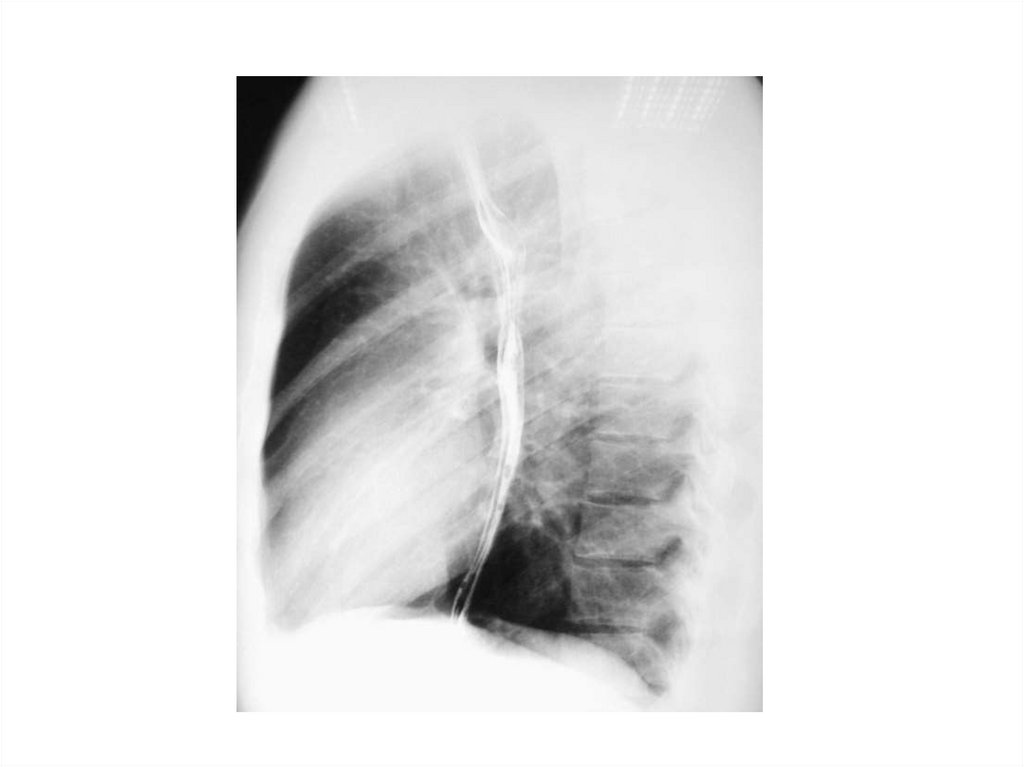

Рентгеноскопия